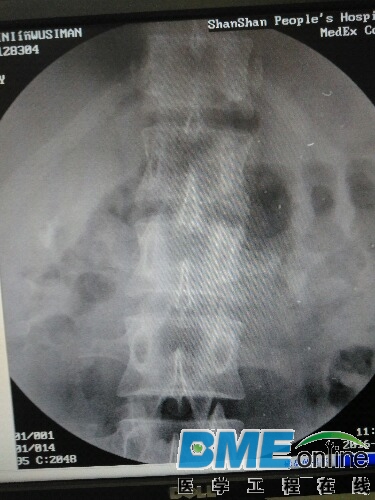

各位大神给简单看看。1.曝光图像模糊不清。2.连续做病人会出现不让曝光,重启后可以曝光

现在只有图像模糊这一现象,自动曝光发现剂量不足所做图像如下,

所做图像看着不是很清楚